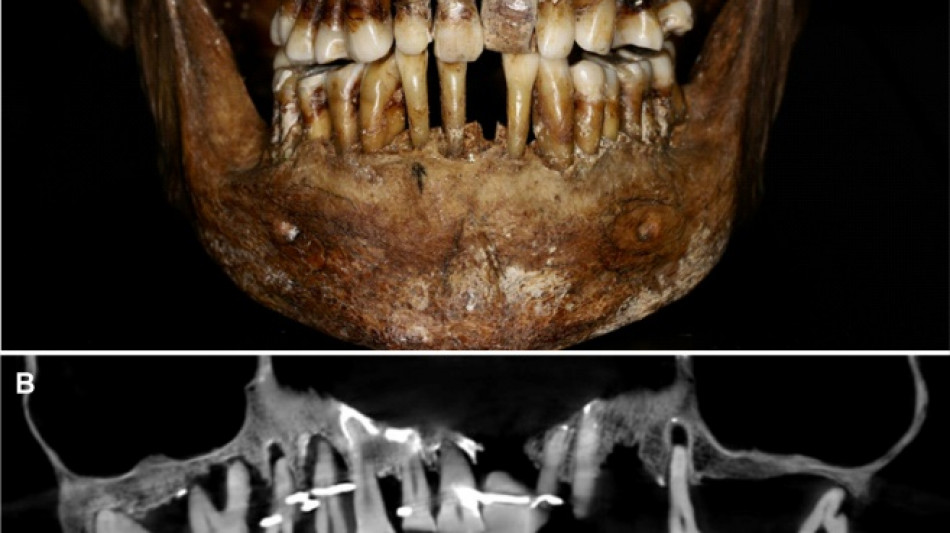

French aristocrat's golden dental secret revealed 400 years on / Photo: Handout - INRAP/Rozenn Colleter/AFP/File

Thirty-five years later, a team of archaeologists and dentists have identified that d'Alegre suffered from periodontal disease that was loosening her teeth, according to a study published in the Journal of Archaeological Science: Reports this week.

A "Cone Beam" scan, which uses X-rays to build three-dimensional images, showed that gold wire had been used to hold together and tighten several of her teeth.

She also had an artificial tooth made of ivory from an elephant -- not hippopotamus, which was popular at the time.